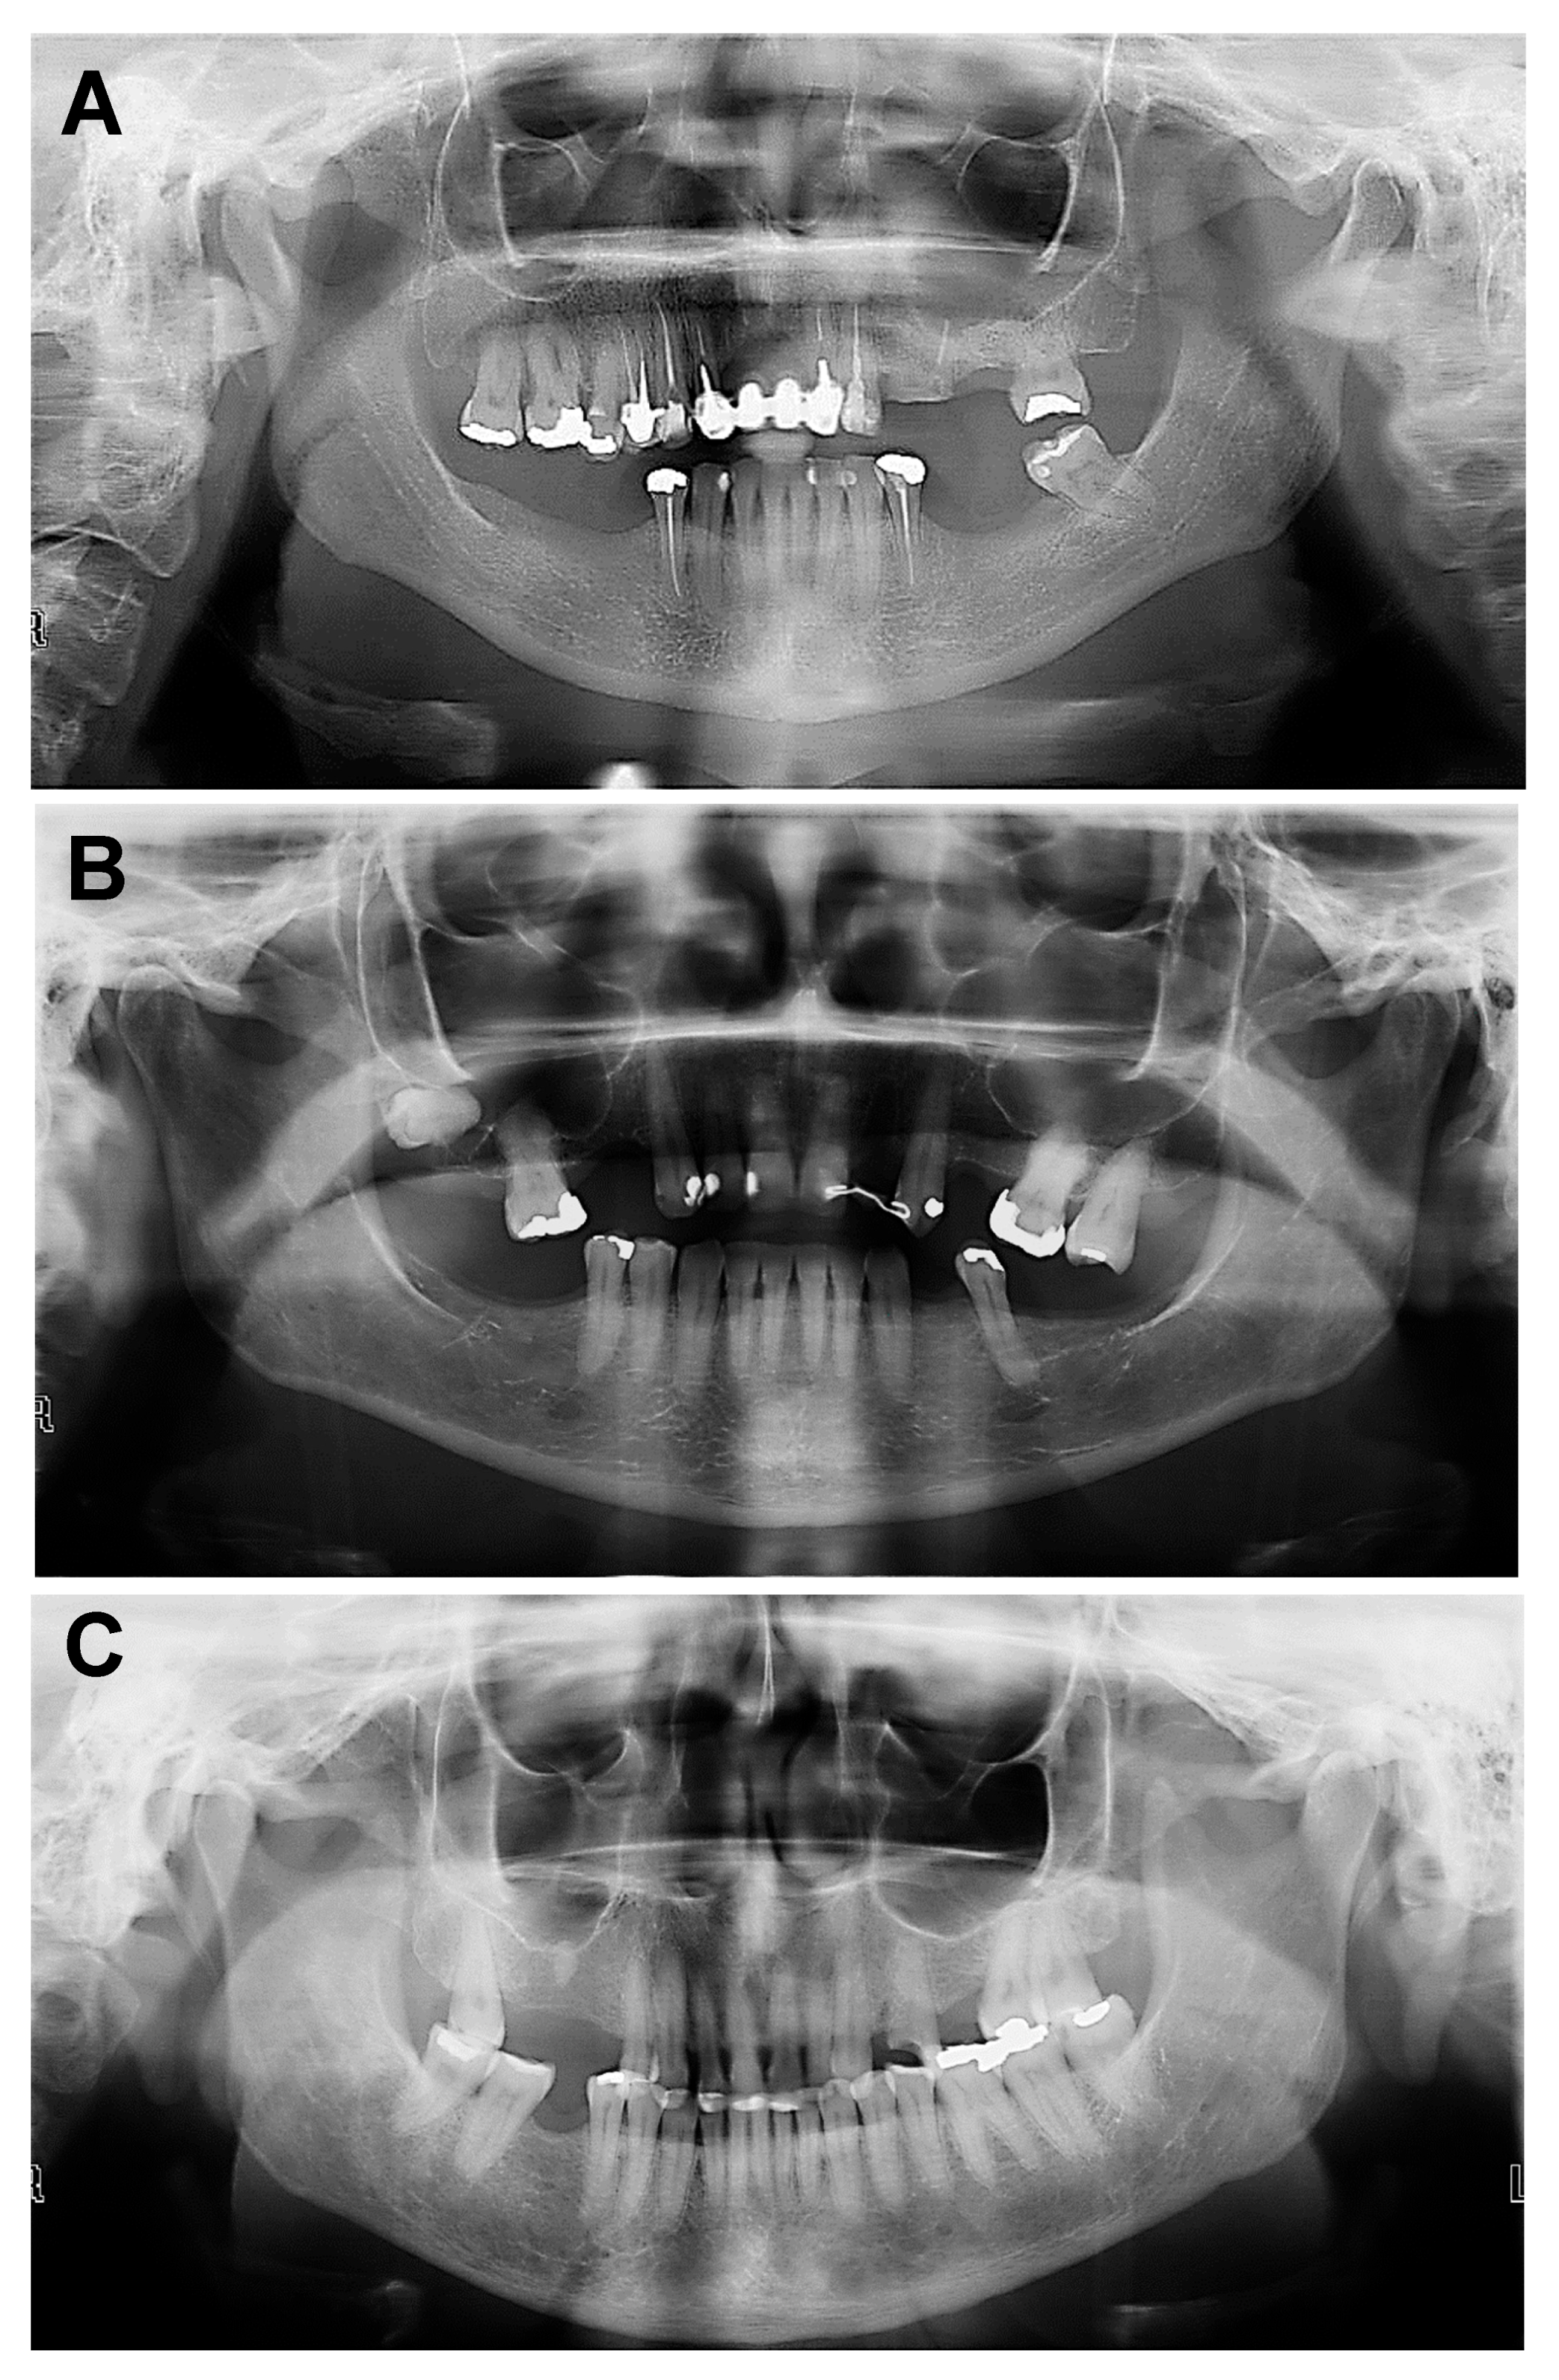

| C1 | (Normal)—Smooth and regular cortical |

| C2 | (Osteopenia)—Cortical with semilunar defects (lacunar resorption) |

| C3 | (Osteoporosis)—Clearly porous cortical layer and its thickness is tapered and reduced |